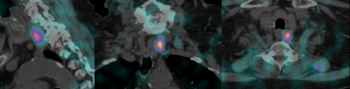

Exemples d’images obtenues par le service de Médecine Nucléaire de l’hôpital de Citadelle

Grâce aux technologies d’imagerie hybride, il est possible de combiner en un seul examen une imagerie fonctionnelle et une imagerie anatomique, améliorant ainsi la précision du diagnostic et le suivi médical.

• Neurologie nucléaire : examens spécialisés (Datscan, HMPAO, MIBG, FDG, …)